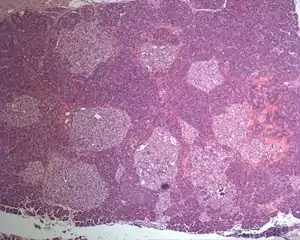

| Photographic image of the numerous islets of various sizes in the pancreas of a patient with Mahvash disease | |

Most patients with Mahvash disease are diagnosed in adulthood. Patients with Mahvash disease usually present with vague abdominal discomfort. Imaging with CT or MRI identifies a very large pancreas with one or more tumors. Biochemical testing shows marked hyperglucagonemia (hundreds-fold elevated). If the tumors are resected, they are found to be neuroendocrine tumors that usually express glucagon. In the tumor margin, pancreatic alpha cell hyperplasia is pervasive, numerous large islets composed of mostly alpha cells are evident, and multiple microadenomas and small neuroendocrine tumors often are present. The pancreatic neuroendocrine tumors are the main health concern for patients with Mahvash disease. Although the tumors commonly are indolent, death due to liver metastasis has been reported.